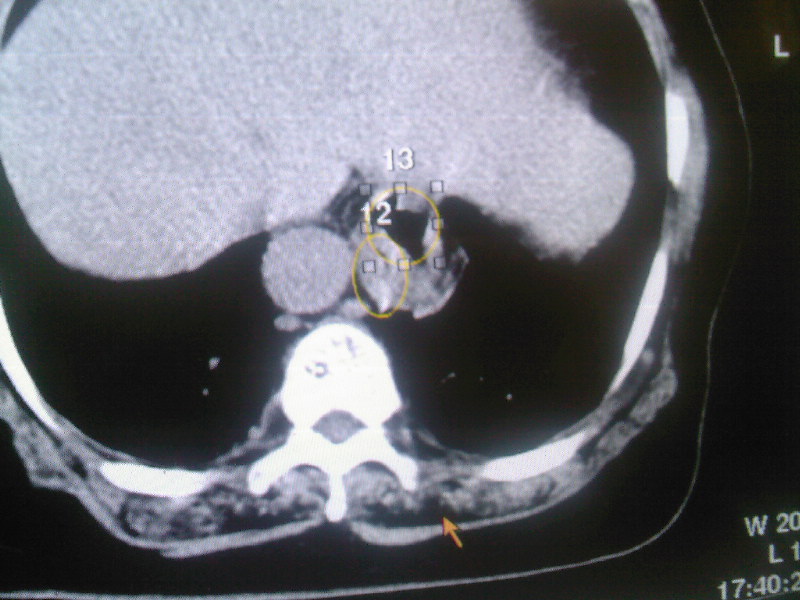

食管下段近贲门处可见前方一限局性空腔影。想临食管避受压,且与食管分界不清,跨与食管裂孔处,顶部位于中后纵膈,请指教

食管壁不规则增厚,年龄大考虑为占位肿瘤性病变

食管壁不规则增厚,年龄大考虑为占位肿瘤性病变  ,怎么没有做钡餐呢?